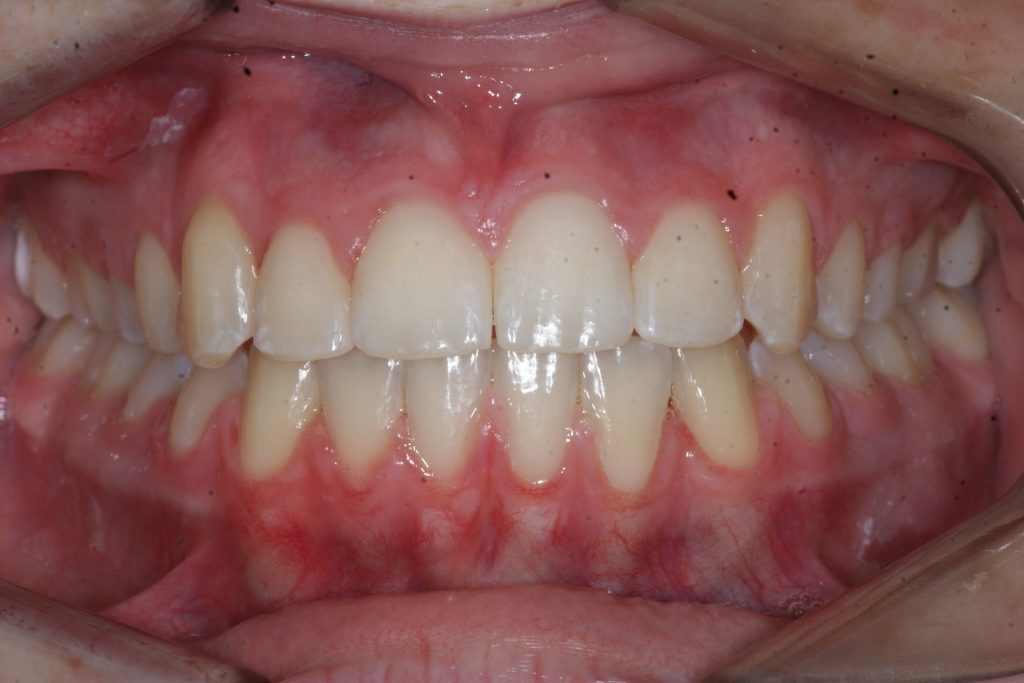

Correction d’une malocclusion de type Classe II subdivision avec canine ectopique (#14).  Des appareils fixes (boîtiers) et l’extraction d’une prémolaire (#15) furent nécessaires pour améliorer ce sourire.  Traitement chez une adolescente, réalisé en 21 mois.